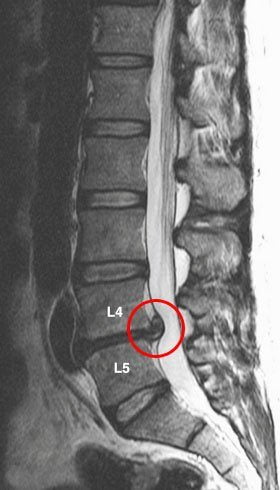

Грыжа в поясничном отделе позвоночника

Межпозвонковый диск, расположенный между смежными позвонками, может выпячиваться с правой стороны позвоночника. Межпозвонковая грыжа может вызывать тупую, ноющую боль в пояснице вследствие защемления спинно-мозгового корешка в узком фораминальном отверстии. Боль в пояснице справа может сочетаться с болью в ягодице и правой ноге до стопы.

Просвет позвоночного канала может сужаться из-за межпозвонковой грыжи, костных разрастаний и других проблем, приводя к боли в пояснице справа, а также к корешковой боли и/или слабости в правой ягодице и ноге;

Синдром конского хвоста

Одно из самых тяжелых осложнений грыжи диска поясничного отдела позвоночника. Возникает при больших размерах межпозвонковой грыжи или при грыже среднего размера на фоне узкого позвоночного канала. Симптомы могут начаться внезапно или развиваться постепенно, но в конечном итоге происходит стойкое нарушение функции тазовых органов и /или нарушения функции нижних конечностей, наиболее часто парез стопы. Состояние требует немедленной, в основном, хирургической помощи в течение ограниченного времени. Синдром конского хвоста может быть вызван и другими причинами, например, наличием опухоли в просвете позвоночного канала, туберкулезом позвоночника и так далее.